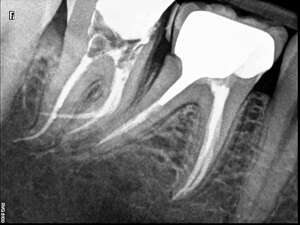

Cas du patient 1

Cas du patient 2

Avant

Après